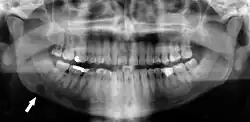

Panoramic radiograph showing horizontally impacted lower wisdom teeth.